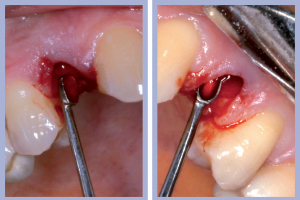

- Figg. 8a, b – Mappatura alveolare tramite sonda parodontale

- Figg. 9a, b – Preparazione del sito di destra

- Figg. 10a, b – Preparazione del sito di sinistra